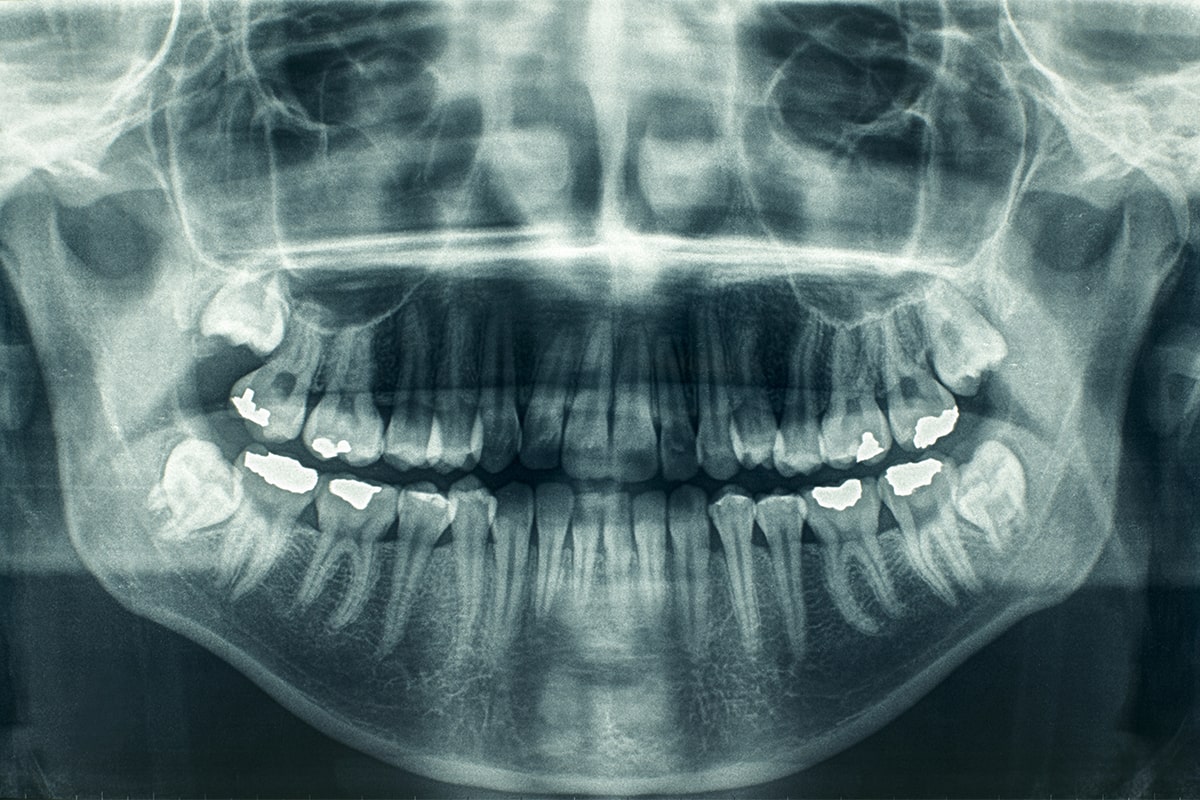

Képalkotó eljárások

- CBCT

- nagy felbontású panoráma röntgen

- teleröntgen

- periapicális felvétel